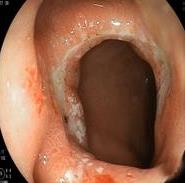

• 内镜诊断和治疗十二指肠黏膜下恒径动脉破裂出血并活动性出血的价值(附6例报告)

摘要:目的 探讨内镜诊断和治疗十二指肠黏膜下恒径动脉破裂出血并活动性出血的价值。方法 回顾性分析2015年6月-2023年1月该院经内镜确诊十二指肠黏膜下恒径动脉破裂出血并活动性出血的6例患者的临床资料。总结临床表现、内镜下特征和治疗转归。结果 于24 h内完成急诊内镜检查,证实6例均为单纯十二指肠黏膜下恒径动脉破裂出血,并成功行内镜下钛夹止血治疗。结论 内镜诊断十二指肠黏膜下恒径动脉破裂出血所致的大出血,具有较高的价值。此外,于内镜下及时采取积极、有效的干预措施,可快速止血,降低死亡率。值得应用于临床。